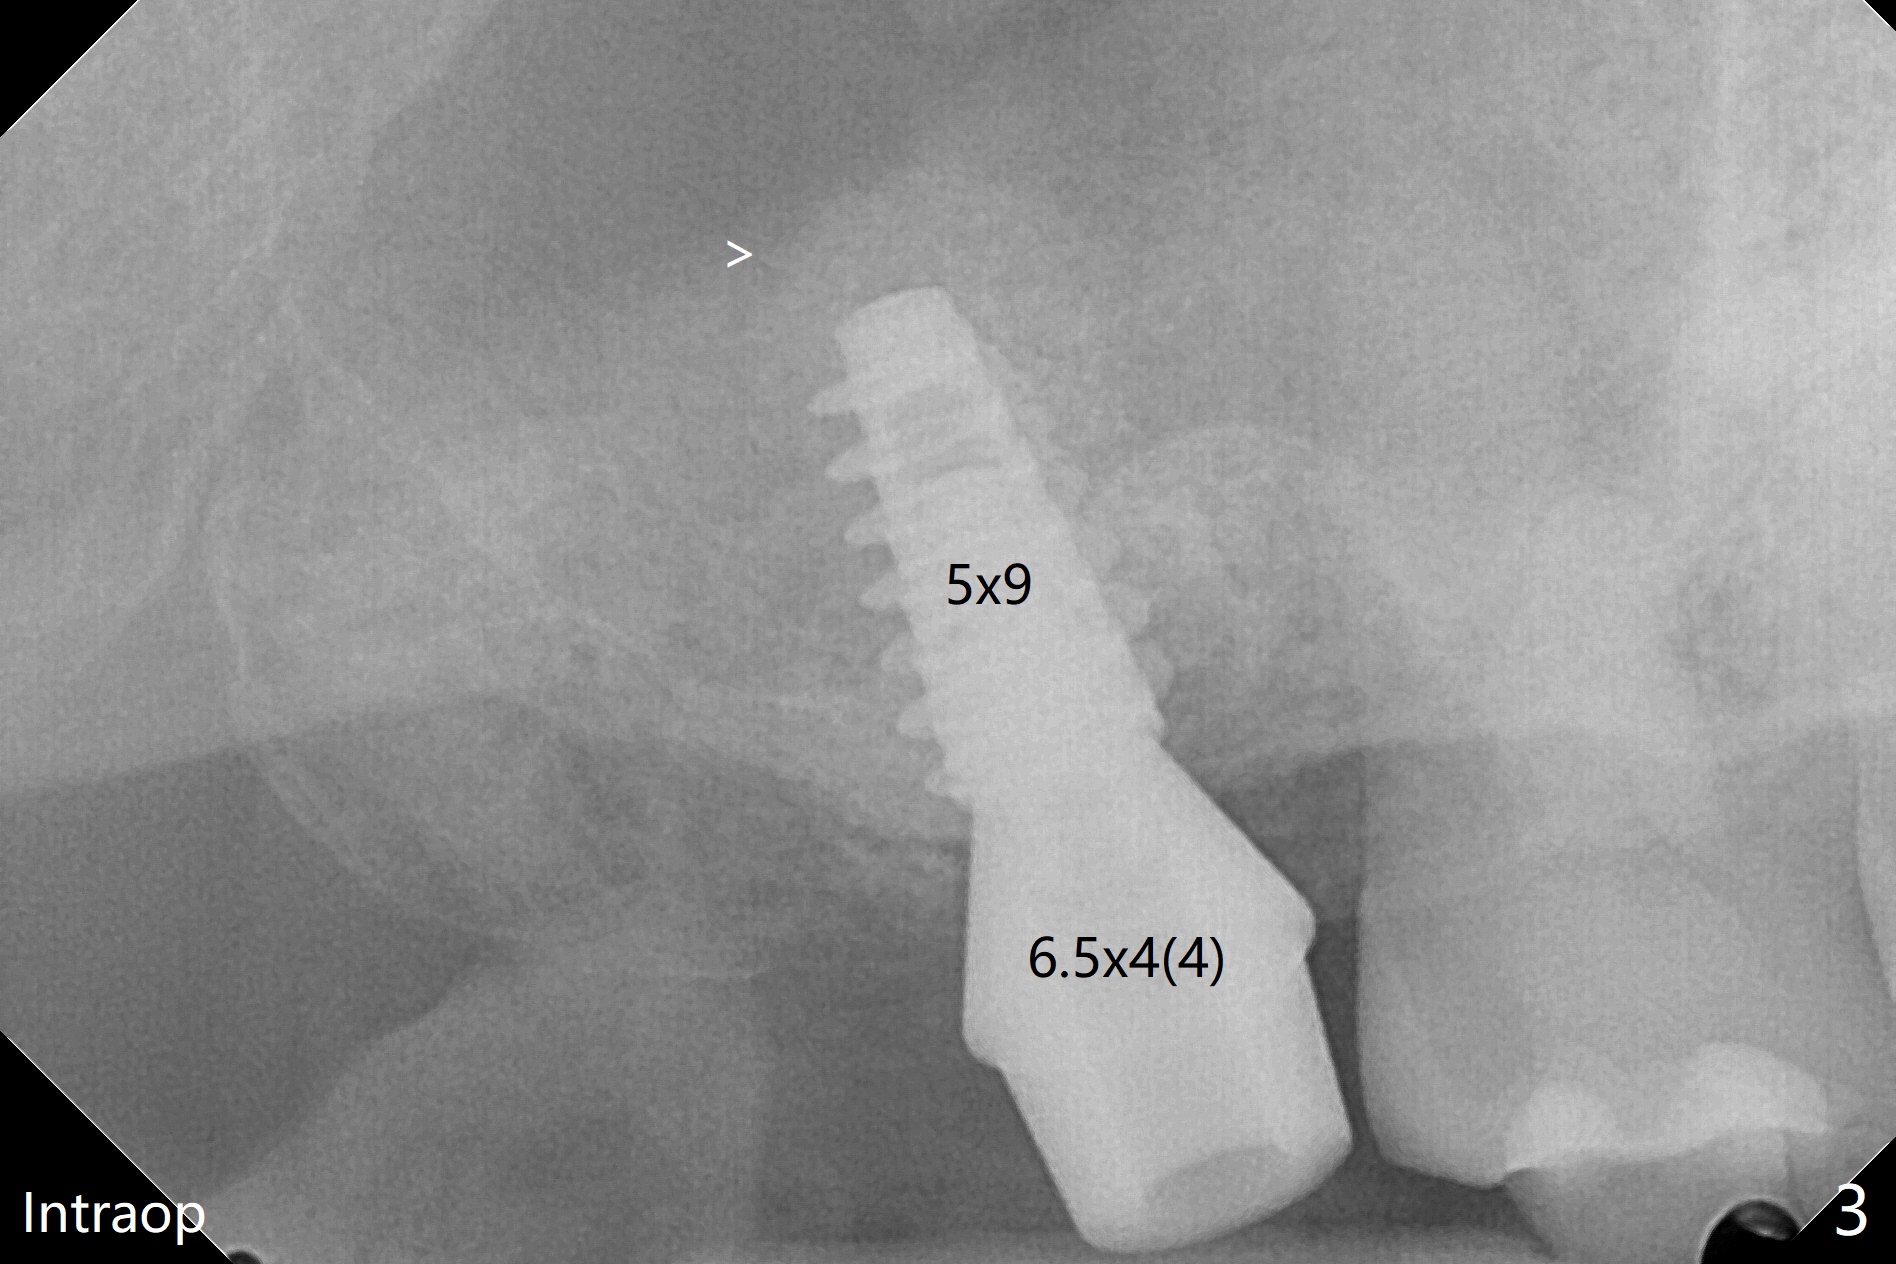

在导航协助下,我们可以一期准确进行上颌窦提升,即刻种植,即刻修复。56岁男(吸烟)右侧上颌窦有粘液囊肿,右上七牙齿折裂(图一(术前):^),CT检查表明植体植入腭侧牙槽窝比较合适(图一:>)。为了减少对囊肿损伤,我们使用导板(图二 *)完成初步钻洞,接近上颌窦底板,然后放置粘性骨(>),用4x10毫米dummy(报废)植体慢速(15 RPM)旋入进行内提升,同时准确控制深度。再次放置骨粉,使用4.5x10毫米报废植体上推;最后放置骨粉后(图三 >),植入正式植体(5x9毫米,扭力大于35Ncm)和修复基台(6.5x4(4)),怀疑后者没有完全就位,后来使用小的基台(图四,并且调整高度),植体和基台周围放置骨粉(*),然后安置临时牙冠。咬颌面没有接触,临时牙冠主要目的是防止骨粉丢失。反复告诉病人不能咬东西。术后两周病人主诉临时牙冠太大,试图减少颊舌侧向,不幸的是却减少近中远中向,造成临时牙冠不稳定。一周后牙冠和基台松动,取出,放置愈合螺帽,牙槽窝基本愈合。病人将术后近四个月复诊,拍摄根尖片和咬翼片,如果骨质愈合良好,尝试在尚未完全愈合的伤口放置小号愈合基台。术后5个月牙冠粘固后拧紧植体松动,取出(图五(*:缺损)),植骨。四个月后骨质高度近5毫米(图六)。再次植入尽量避免窦膜穿孔(粘液囊肿),塞入PRF膜。Return to Upper Molar Immediate Implant, Prevent Molar Periimplantitis (Protocols, Table) No Deviation 不理想病例 开场白Xin Wei, DDS, PhD, MS 1st edition 08/10/2020, last revision 06/12/2021